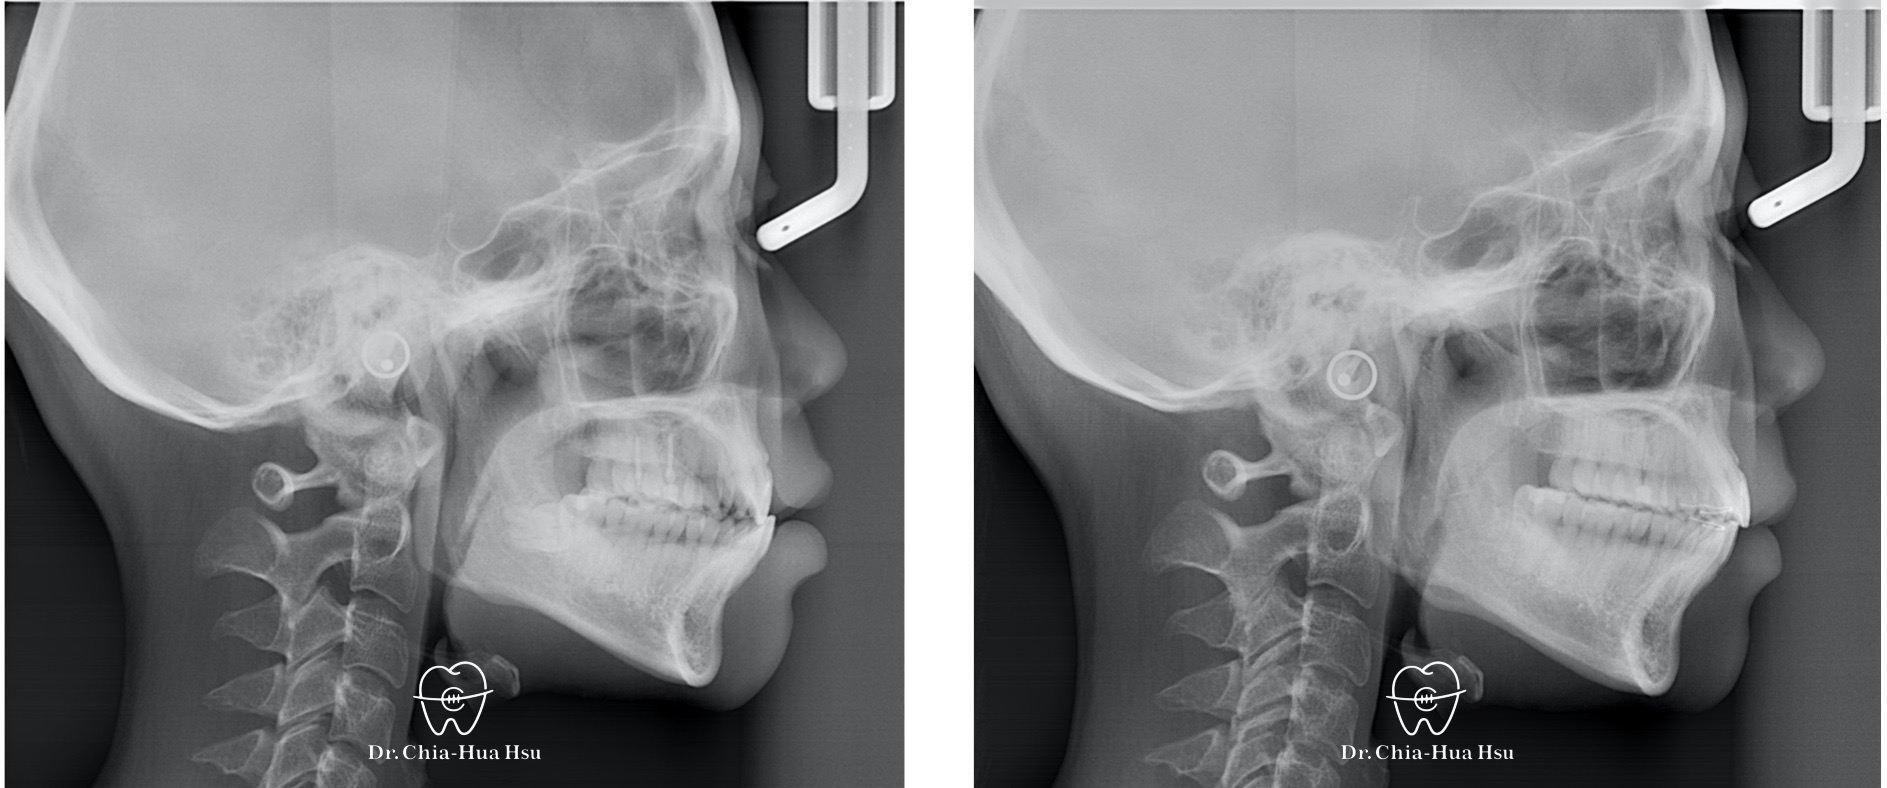

治療前

治療後